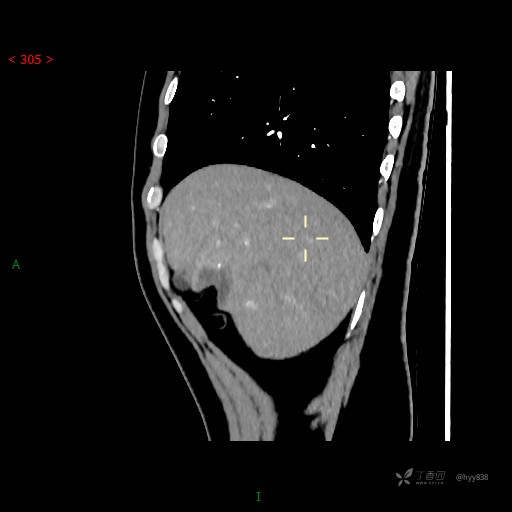

年轻男性,肝脏孤立结节、邻近包膜如此内陷,不知“坑”为何物---(结果公布)

肝脏CT平扫